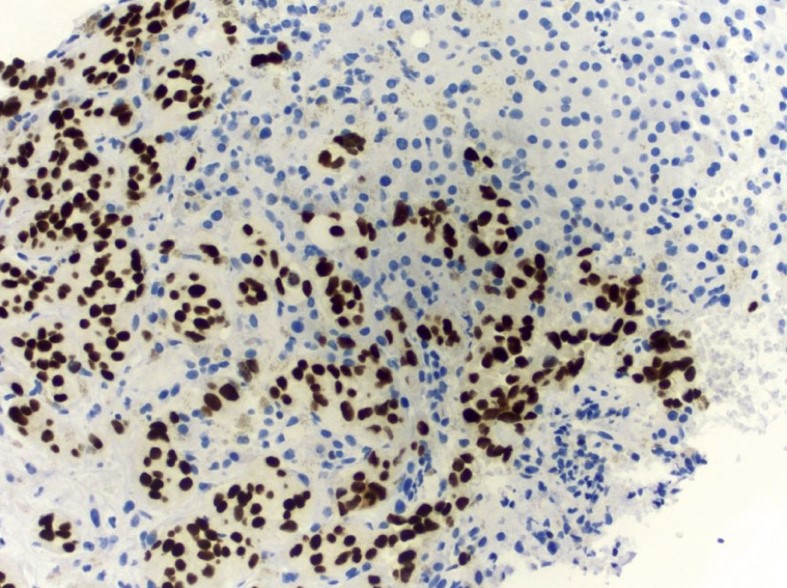

Microscopic (histologic) images

Contributed by Emily S. Reisenbichler, M.D., Andrey Bychkov, M.D., Ph.D., Maria Tretiakova, M.D., Ph.D. and Debra Zynger, M.D.

Interpretation

- Nuclear stain

Positive staining - tumors

- Breast cancer, invasive (72 - 94%) (Mod Pathol 2010;23:654, Am J Clin Pathol 2012;138:57), well differentiated > poorly differentiated; more sensitive than GCDFP-15 and mammoglobin in staining of metastatic breast carcinoma (Ann Diagn Pathol 2015;19:6)

- Primary and metastatic urothelial carcinoma (67 - 93%) (Am J Surg Pathol 2007;31:673, Am J Surg Pathol 2013;37:1876)